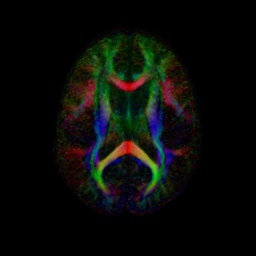

An initial test was performed by using the procedure on a set of images of healthy subject at age one year. The results of the tensor averaging are shown on the right. Tractography was also performed on the mean atlas image as shown.

We have begun to apply the DTI atlas building procedure to data provided by the PNL. A combined set of DTI scans from control and Schizophrenic subjects were aligned using the procedure described above. In the atlas space the SZ and CNTL groups are processed to produce voxel-wise statistics for each group. The figure below shows colored FA and mean diffusivity slices for both the CNTL and SZ group. Preliminary work is now being done on region of interest (ROI) hypothesis testing between the two populations.